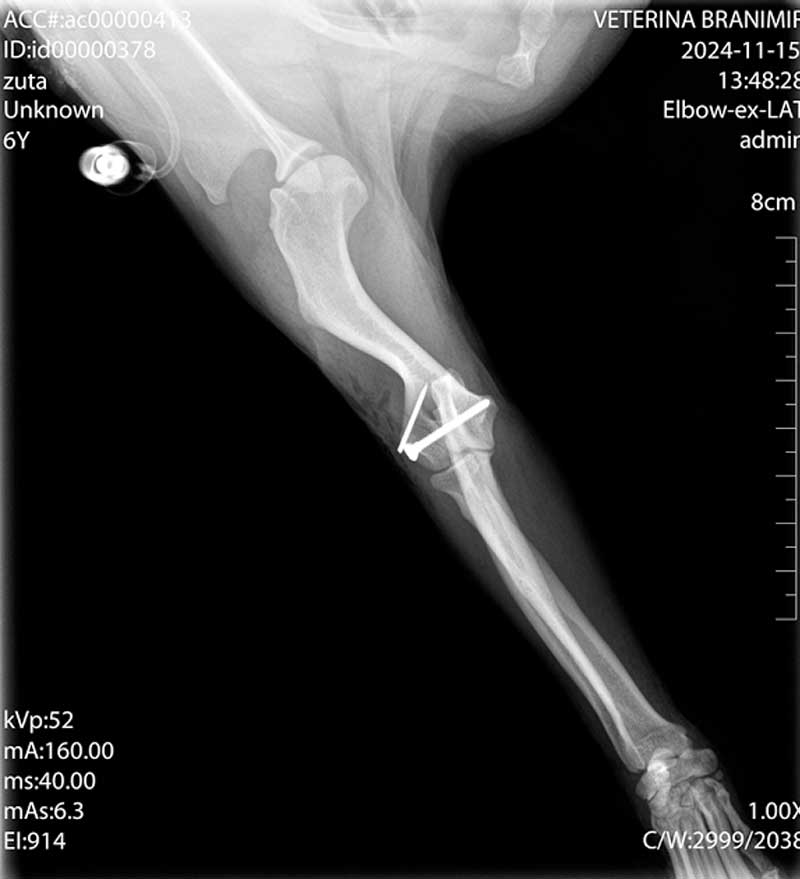

Dijagnoza se postavlja rendgenskim snimkama koje pokazuju lokaciju i tip prijeloma.

Liječenje može biti konzervativno, pomoću gipsa ili udlage, ili kirurško, uključujući pločice, vijke, čavle ili vanjsku fiksaciju.

Kirurško liječenje omogućuje precizno poravnanje kostiju i stabilnost tijekom cijeljenja, što skraćuje vrijeme oporavka.